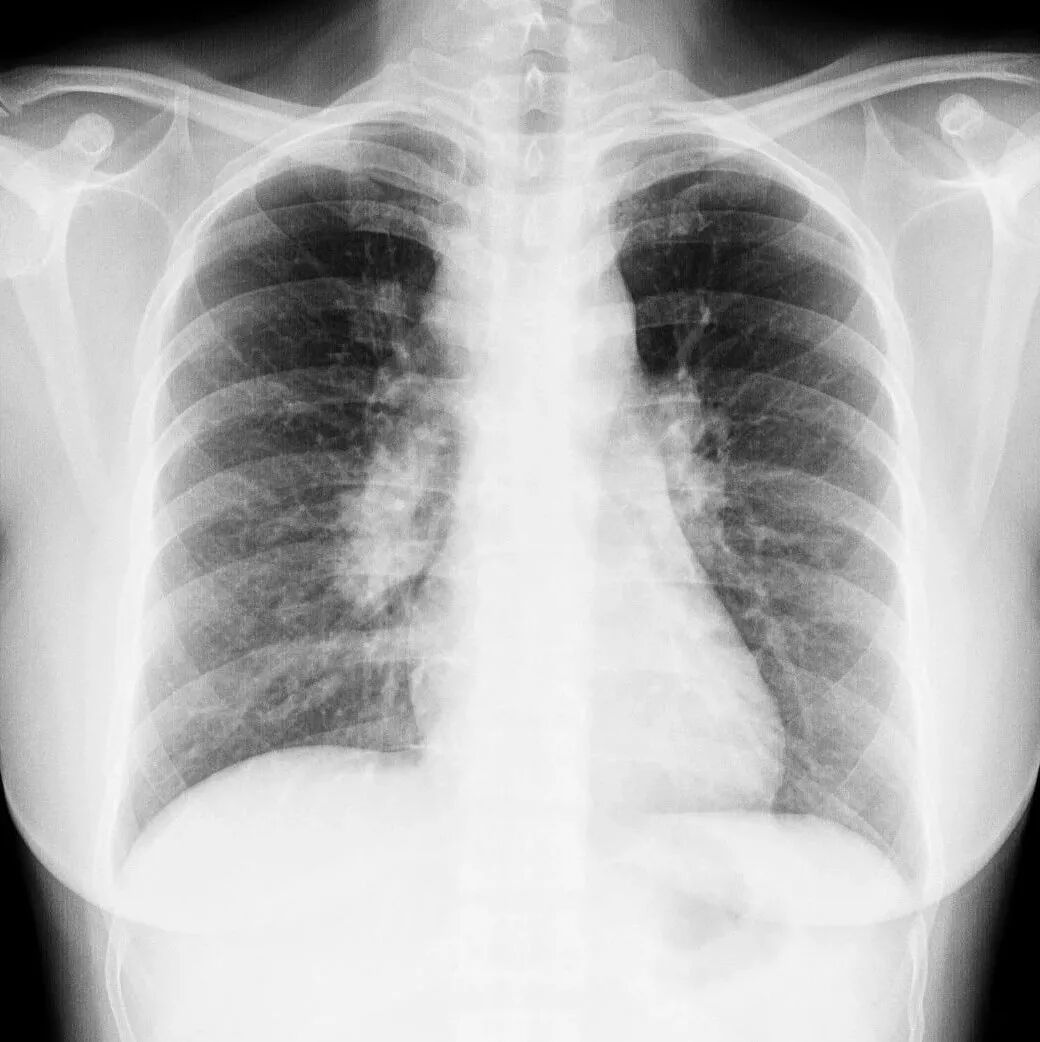

胸透和胸片主要用于检查诊断肺部疾病、心脏的大小、肋骨、胸膜、胸壁纵隔、支气管。为减少X线的损害,患者做检查不宜过多。

胸片DR和胸透还是有很大的区别的,当然它们都是检查胸部,也就是看肺这一块的。但是它们的区别还是比较大的,首先第一点它的辐射剂量有很大的差别,胸片DR,它的辐射剂量是非常的小,而胸透相对来说就要大一些了,主要是跟它辐射的时间有关系。

做胸片DR检查的话,它辐射的时间是非常短的,一般也就是零点零几秒的时间,非常的短,而胸透检查它这个辐射时间相对来说就要长一些了,一般是需要十秒钟的时间。当然如果发现有可疑的病灶,可能需要看的时间要更长一些了。正因为是这样,所以现在很多医院已经基本上取消了胸透检查了,都是用胸片来进行替代。

胸片的话一般是可以照出一张片子来,而胸透只是医生通过目视,通过眼睛来看,看完之后得出一个纸质报告,是没有这种片子的。

最常用X光片、CT大致了解选X光片,细致分析选CT肺的检查一般不选核磁

胸部